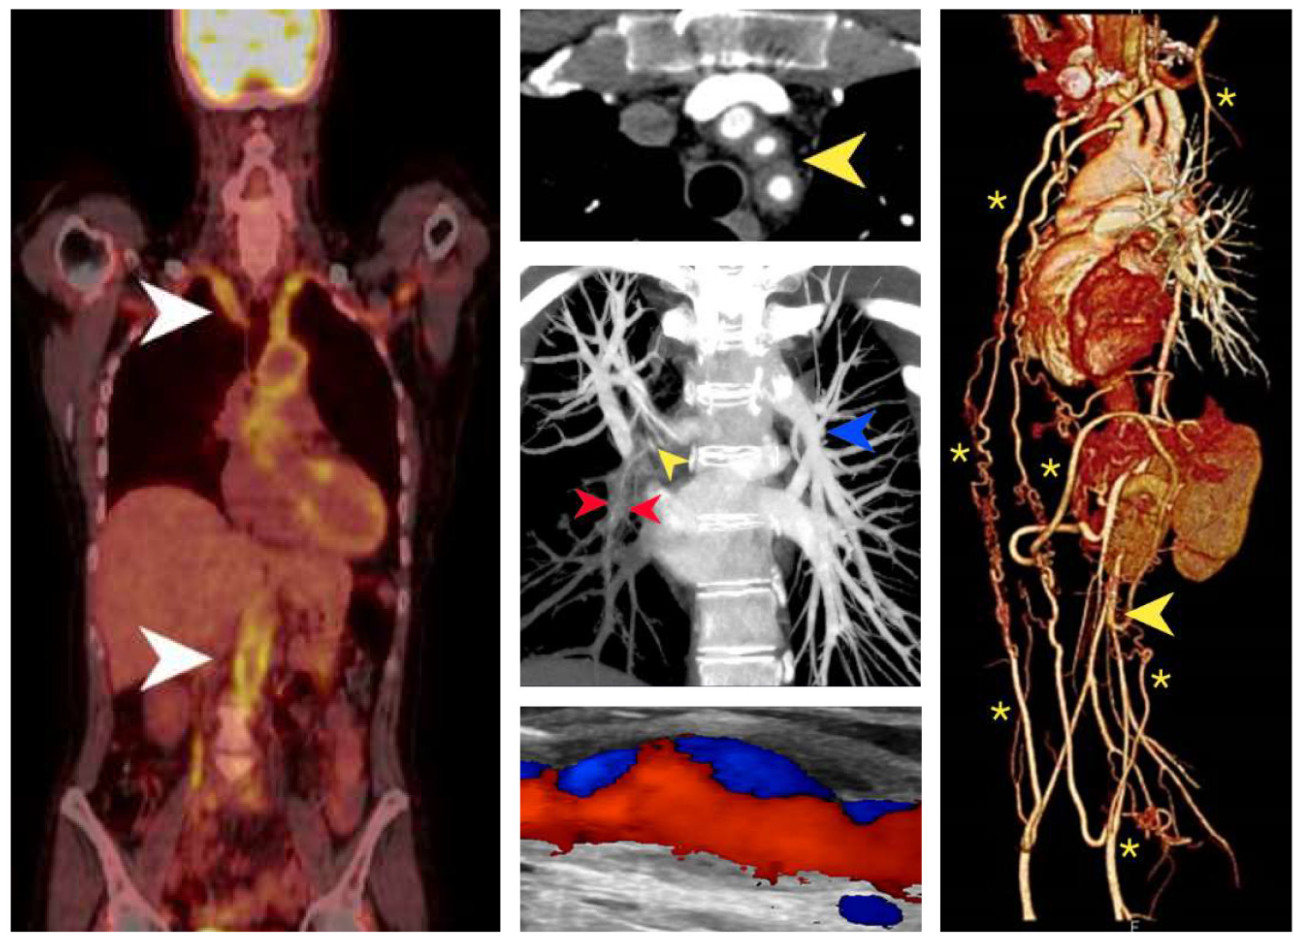

In a paper recently published in JACC Cardiovascular Imaging, we presented a series of images which summarise the various imaging modalities utilised in the management of Takayasu’s arteritis (TA)—a rare autoimmune vasculitis which affects the aorta and its major branches. Immunosuppressive therapy is employed to suppress inflammation, to prevent arterial injury and encourage positive remodelling. These images represent the 20-year cumulative experience of the multidisciplinary team at Imperial College NHS Trust treating this rare disease.

The natural history of TA is apparent through these images as we outline its diagnosis, extent and pattern, monitoring, and long-term outcomes. Early diagnosis can be facilitated with positron-emission tomography, magnetic resonance imaging (MRI) / angiography (MRA), computed tomography angiography, and high-resolution ultrasound. Furthermore, MRI and MRA remain invaluable for interval monitoring for treatment responses and promptly detecting signs of disease progression without ionising radiation. Other specialised imaging modalities are occasionally useful such as Tc99m-DSMA radionucleotide scanning to determine differential renal function in those with renal artery stenosis, and Tc99m HMPAO SPECT imaging to assess cerebral perfusion for those presenting with cerebral ischaemia, respectively. Integrated non-invasive imaging has transformed the approach to TA allowing for optimised clinical care in this patient cohort.

A. FDG-PET/CT imaging demonstrates intense homogenous tracer uptake throughout the vessel wall, consistent with aortitis and subclavian arteritis (arrows). B. Supra-aortic artery arteritis, with cuffing of the great vessels by inflammatory tissue is shown here by Computed tomography (CT) angiography. C. Pulmonary artery involvement is seen in up to 50% of TA patients. This CT pulmonary angiogram demonstrates severe stenosis of the right lower lobe pulmonary artery (red and yellow arrows). D. This high resolution ultrasound image with colour Doppler reveals concentric, homogenous thickening of the common carotid artery wall with evidence of focal arterial wall dilatation and disturbed blood flow. E. Tissue ischemia may be an important driver for collateral artery formation which can significantly reduce ischemic symptoms. The thoracic MRA 3D volume rendered reconstruction shows extensive disease of the aorta culminating in distal occlusion (arrow) and extensive collaterals (asterisks) which revascularise the gastrointestinal and the lower limb circulation.